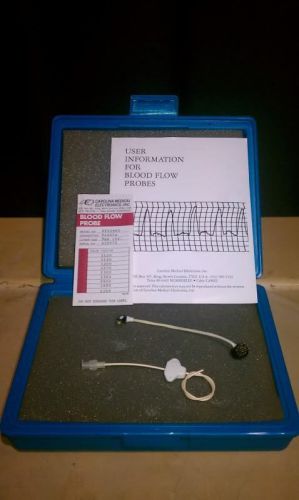

CME: Carolina Medical, Model EP408 H Blood Flow Probe

CME: Carolina Medical, Model EP108 SC Blood Flow Probe